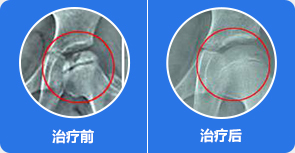

修复坏死骨质原因

清理、修复受损骨质,促进新骨再生

通过彻底清除关节腔内积液、炎症及游离物质,促进坏死骨质再生,改善跛行、受限症状,避免置换。

通过可视微创针镜,精准定位关节腔内炎症、积液及游离物质位置,有效清理,同时松解关节腔内粘连组织,为股骨头自我修复提供有利环境

治疗前:股骨头塌陷明显,骨质受损严重,关节间隙变窄

治疗中:股骨头受损骨质开始自我修复,关节间隙逐渐正常

治疗后:股骨头骨质修复完整,关节间隙正常